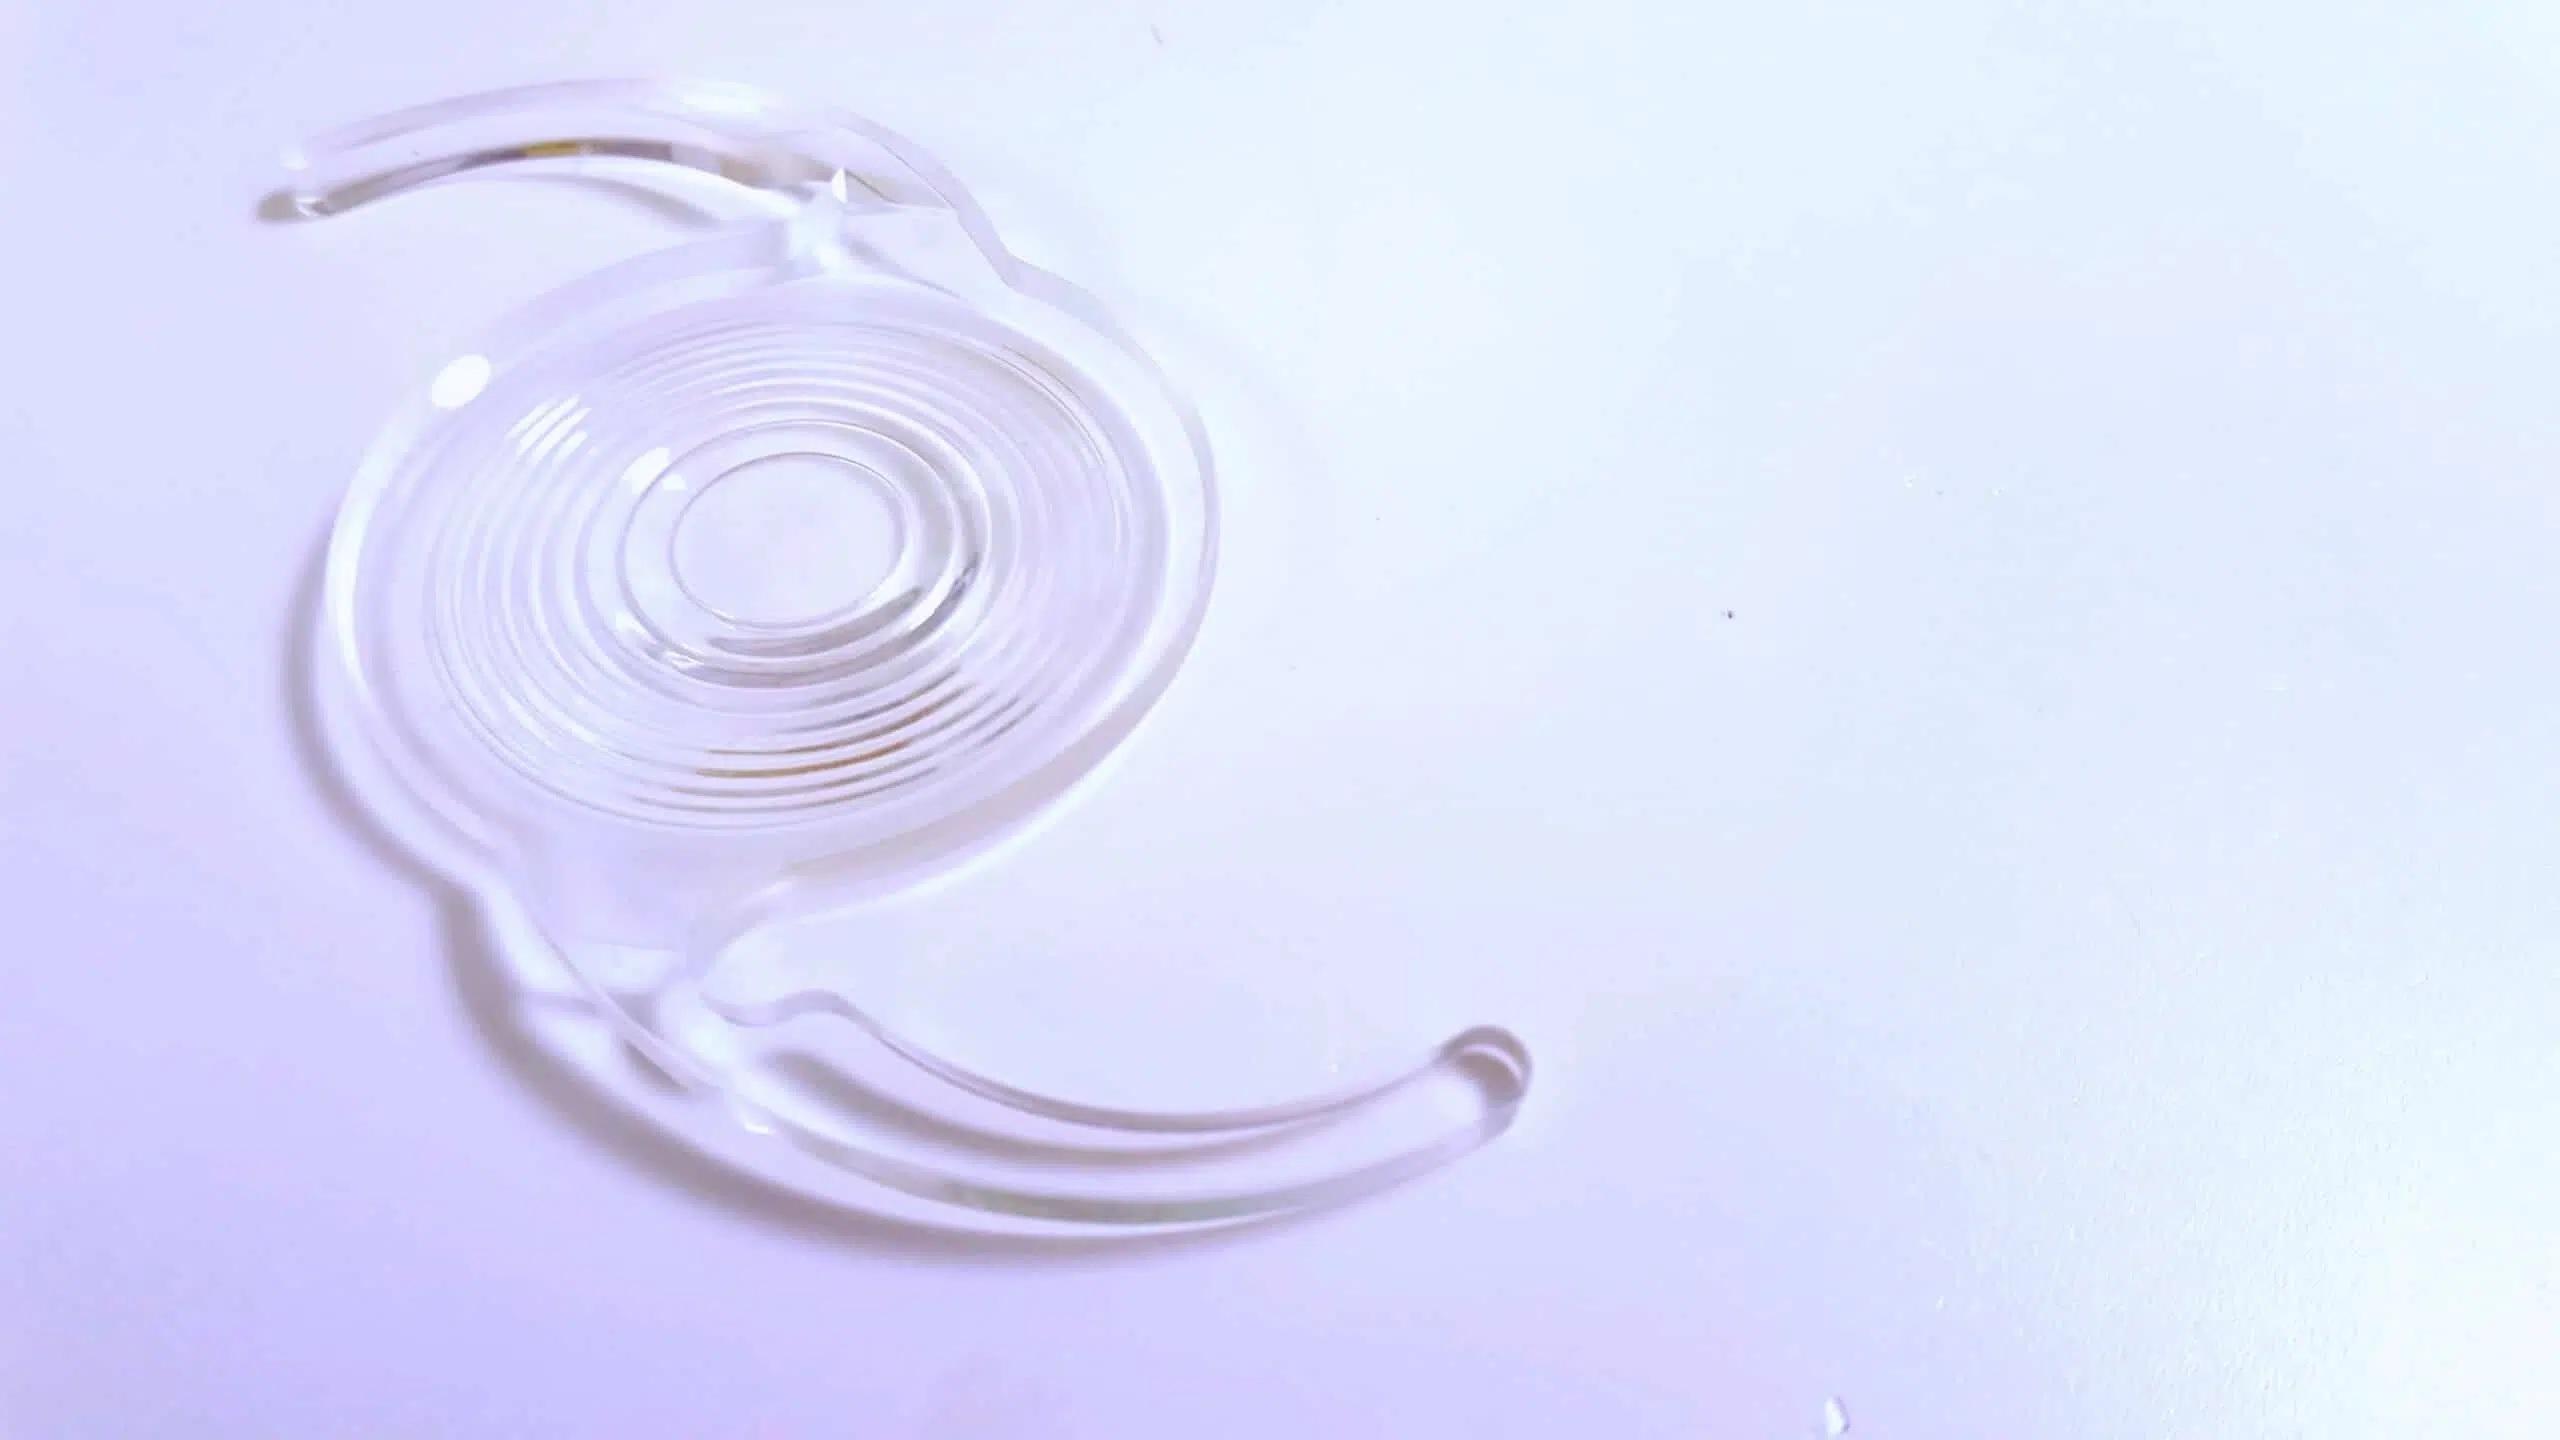

移除混濁的水晶體後,接著須植入人工水晶體以維持視力。

移除混濁的水晶體後,接著須植入人工水晶體以維持視力。雖有普通「球面人工水晶體」可選,但若患者有夜間開車需求,或想一併改善近視、老花、散光等眼疾,可依個人需求與預算選用「功能性人工水晶體」,常見的4種類別如下。

- 非球面人工水晶體:減少夜間炫光問題,可提升行車視線安全,適合晚上需開車族群。

- 散光非球面水晶體:約兩成白內障患者合併有散光問題,植入散光非球面水晶體可同時解決白內障與散光問題,術後不用再佩戴散光眼鏡,適合散光度數大於150度之患者。

- 三焦點非球面人工水晶體:特殊的同心圓構造可讓光線折射或繞射,在眼睛內形成多個焦點,同時看清楚短、中、長距離的物體,白內障、近視和老花3種問題一網打盡。但有夜間眩光問題,較不適合夜間開車族群。

- 延伸焦段非球面人工水晶體:可兼顧中長距離視物,對於駕駛儀表板或電腦螢幕大都能看得清楚,適合大部分晚上需開車的族群。但無法對應看手機的近距離視力需求,術後需搭配老花眼鏡。